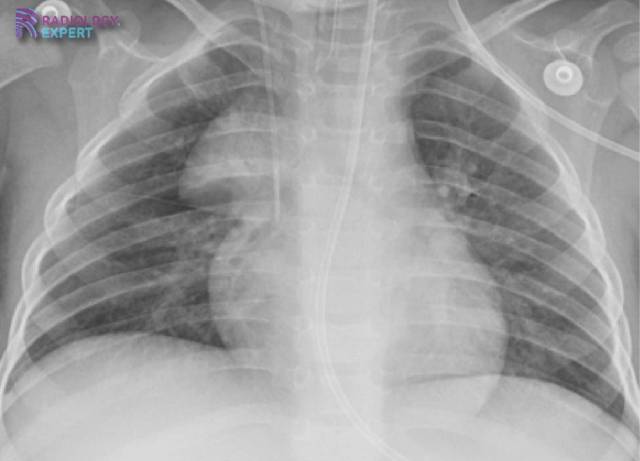

Normal thymus; sail sign Normal thymus; sail sign

Click image to see overlay